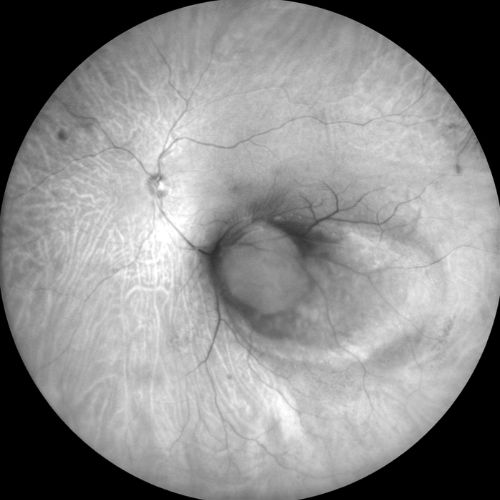

Autofluorescenza

Infrarosso

Fluorangiografia

Fluorangiografie

Retromode

Verde

Rosso